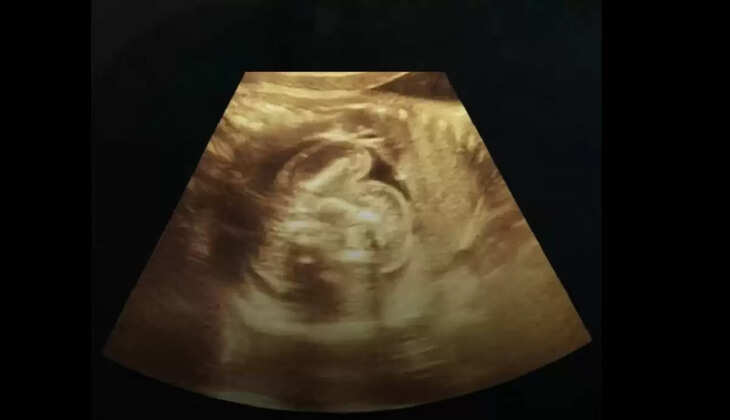

एमआरआई रिपोर्ट में पता चला कि महिला प्रेग्नेंट तो थी, लेकिन उसका गर्भाशय यानी यूट्रस खाली था। हैरानी की बात यह थी कि 12 हफ्ते का गर्भ महिला के गर्भाशय में नहीं, बल्कि उसके लीवर के दाहिने हिस्से में पल रहा था। डॉक्टरों ने यह भी बताया कि भ्रूण पूरी तरह से ज़िंदा था और उसकी धड़कन भी सुनाई दे रही थी।

रेडियोलॉजिस्ट डॉ. के.के. गुप्ता, जिन्होंने इस मामले की पुष्टि की, ने बताया कि वह अपने करियर में ऐसा केस पहली बार देख रहे हैं। उन्होंने कहा, "इतने सालों से काम कर रहा हूं, लेकिन इस तरह का मामला पहली बार देखने को मिला है।" इस तरह की प्रेग्नेंसी को मेडिकल भाषा में एब्डोमिनल प्रेग्नेंसी कहा जाता है, जो बहुत ही दुर्लभ और खतरनाक होती है। पूरी दुनिया में अब तक ऐसे केवल 18 मामले सामने आए हैं, और भारत में यह पहला मामला हो सकता है।

महिला पहले से दो बच्चों की मां है और एक सामान्य गृहिणी है। डॉक्टरों का कहना है कि इस प्रकार की प्रेग्नेंसी को 14 हफ्ते से ज्यादा रखना मां के लिए जानलेवा साबित हो सकता है। डॉ. गुप्ता ने कहा, "जब महिला 22 जुलाई को आई और इस एबनॉर्मल प्रेग्नेंसी का खुलासा हुआ, तो हमने मेडिकल लिटरेचर को खंगाला और पता चला कि लीवर में भ्रूण होना बहुत ही दुर्लभ है।"